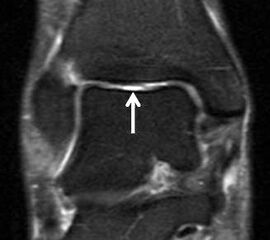

Eine Ursache der falschen Diagnose einer LFTA-Ruptur ist die Fehlinterpretation der physiologische Bandlücke zwischen dem LFTA und der vorderen Syndesmose als traumatischer Banddefekt (Abb. 9 b).

Die Interpretation pathologischer Veränderungen sollte daher immer multiplanar unter Verwendung möglichst dünner Schichtdicken und hoher Ortsauflösungen erfolgen, um Fehldiagnosen zu vermeiden.